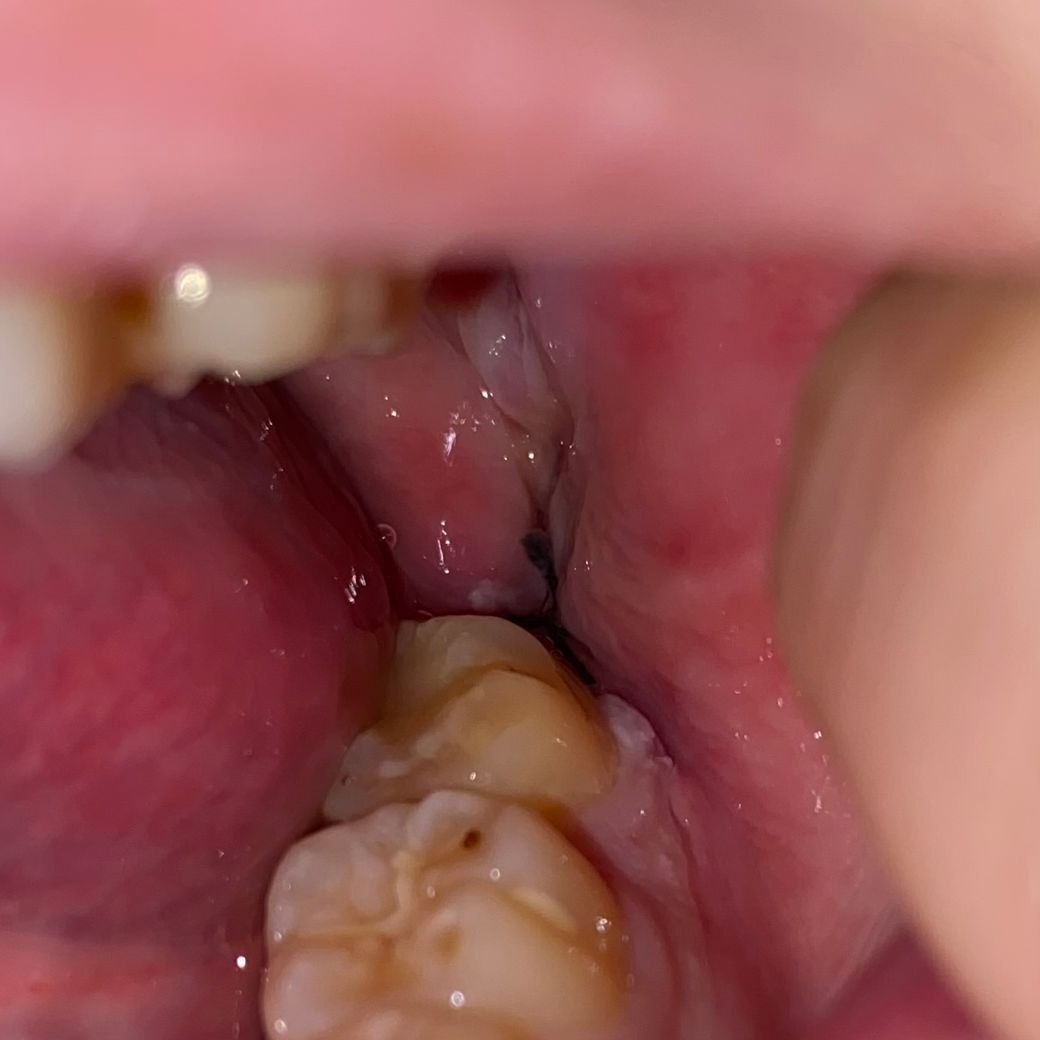

• 1번 째 사진

지난주 토요일에 발치했고 마지막 사진이 현재입니다 잘 낫고있는지 궁금해요... 어제 소독은 받았습니다. 근데 꼬맨 부분이 좀 땡기는데 이것도 맞나요